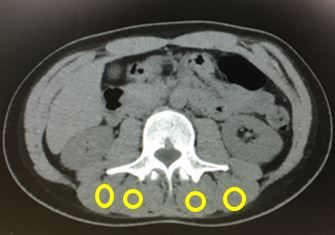

今回私が与えられたテーマは生体肝移植においてドナーの筋肉の質と量がレシピエントの予後に影響を与えるかというものです。実際に配属期間中に行ったことは病棟内の電子カルテを用いて、患者のCT画像から筋肉や皮下脂肪を線で囲みデータを取る作業(筋肉の量はWMI、質はIMACを調べました。) を1~3週目まで行い、データ解析を4週目に、研究内容の発表を最終日に行いました。研究内容について配属期間に行ったことは以上のこととなりますが、期間中に研究内容以外にも沢山のことを学びました。具体的には手術で用いる手技である糸結びの練習、臨床現場での注射や手術(肝腫瘍の切除、生体肝移植) の見学、また病棟内で作業をしていたため医者の方々から「英語をしとった方がいいよー」、「研修するなら~」など色々な話を聞きました。配属期間中の毎日普段の授業では学べない貴重なことを学び、体験させていただきました。

研究室配属を通して1~3週目のデータ取りは同じ作業をひたすら繰り返すため大変でしたが、研究には時間と労力が必要であることを学びました。また、4週目のデータ解析で私自身の取ったデータで女性ドナーのIMACとレシピエントの予後との関連性が見られたときは達成感を得ることができました。研究発表の練習では、1か月間の研究内容について英語のスライドで発表を行い、聞いている方々に研究の内容が伝わるように単語の説明や内容以外の言葉を最小限に抑えるなど、今までの発表では意識していなかったことを指導していただきフォーマルな発表の仕方を知ることができました。また、病棟では研究内容だけでなく、実際の医療現場を見学したり、雰囲気を体験したりすることで将来医者になるための勉強へのモチベーションも高まりました。